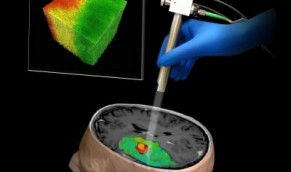

Hinnovic est un blogue indépendant qui a vu le jour en 2008. Jusqu’à la fin de l’année 2022, il s’est consacré à l’analyse des innovations en santé, tout en étant financé exclusivement par des fonds de recherche publics. Sa mission était de contribuer aux discussions collectives sur les innovations affectant la santé des populations et les systèmes de soins.

Vous y trouverez plusieurs textes qui soulèvent des réflexions qui demeurent d’actualité. Bien que les innovations évoluent rapidement, notre capacité à les gouverner de manière responsable représente un défi constant.